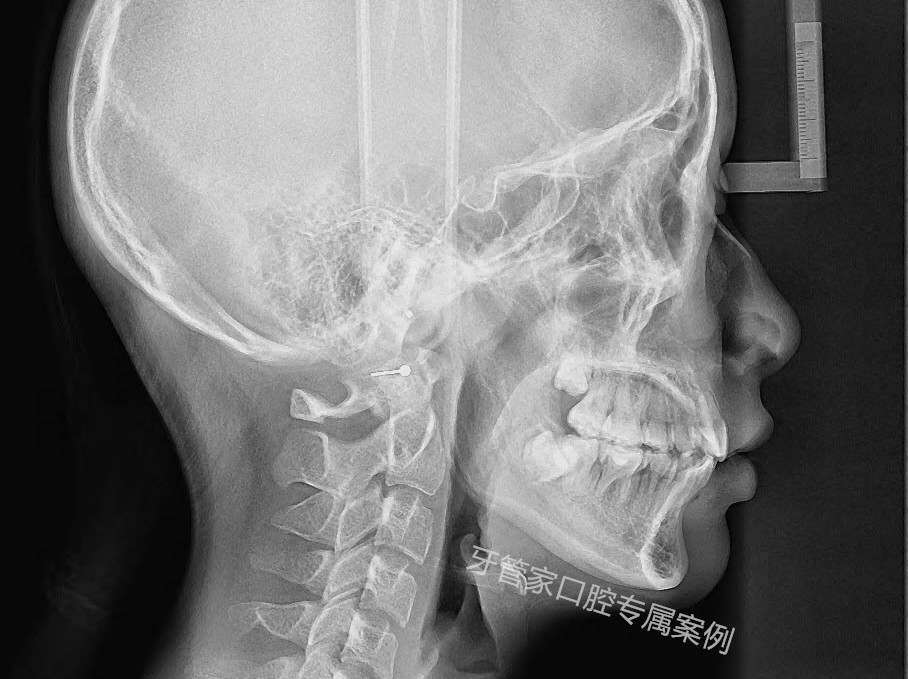

科室配套設(shè)備精良,擁有口腔CBCT、口腔顯微鏡、笑氣鎮(zhèn)痛儀等多種設(shè)備。